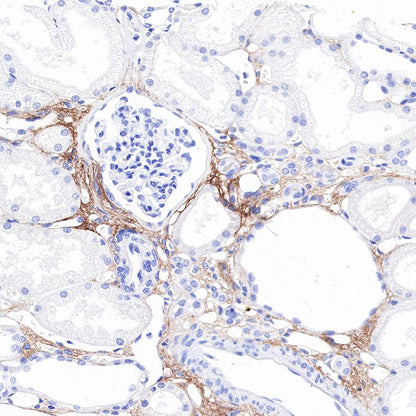

IHC shows positive staining in paraffin-embedded human kidney. Anti-COL3A1(PIIINP) antibody was used at 1/500 dilution, followed by a HRP Polymer for Mouse & Rabbit IgG (ready to use). Counterstained with hematoxylin. Heat mediated antigen retrieval with Tris/EDTA buffer pH9.0 was performed before commencing with IHC staining protocol.